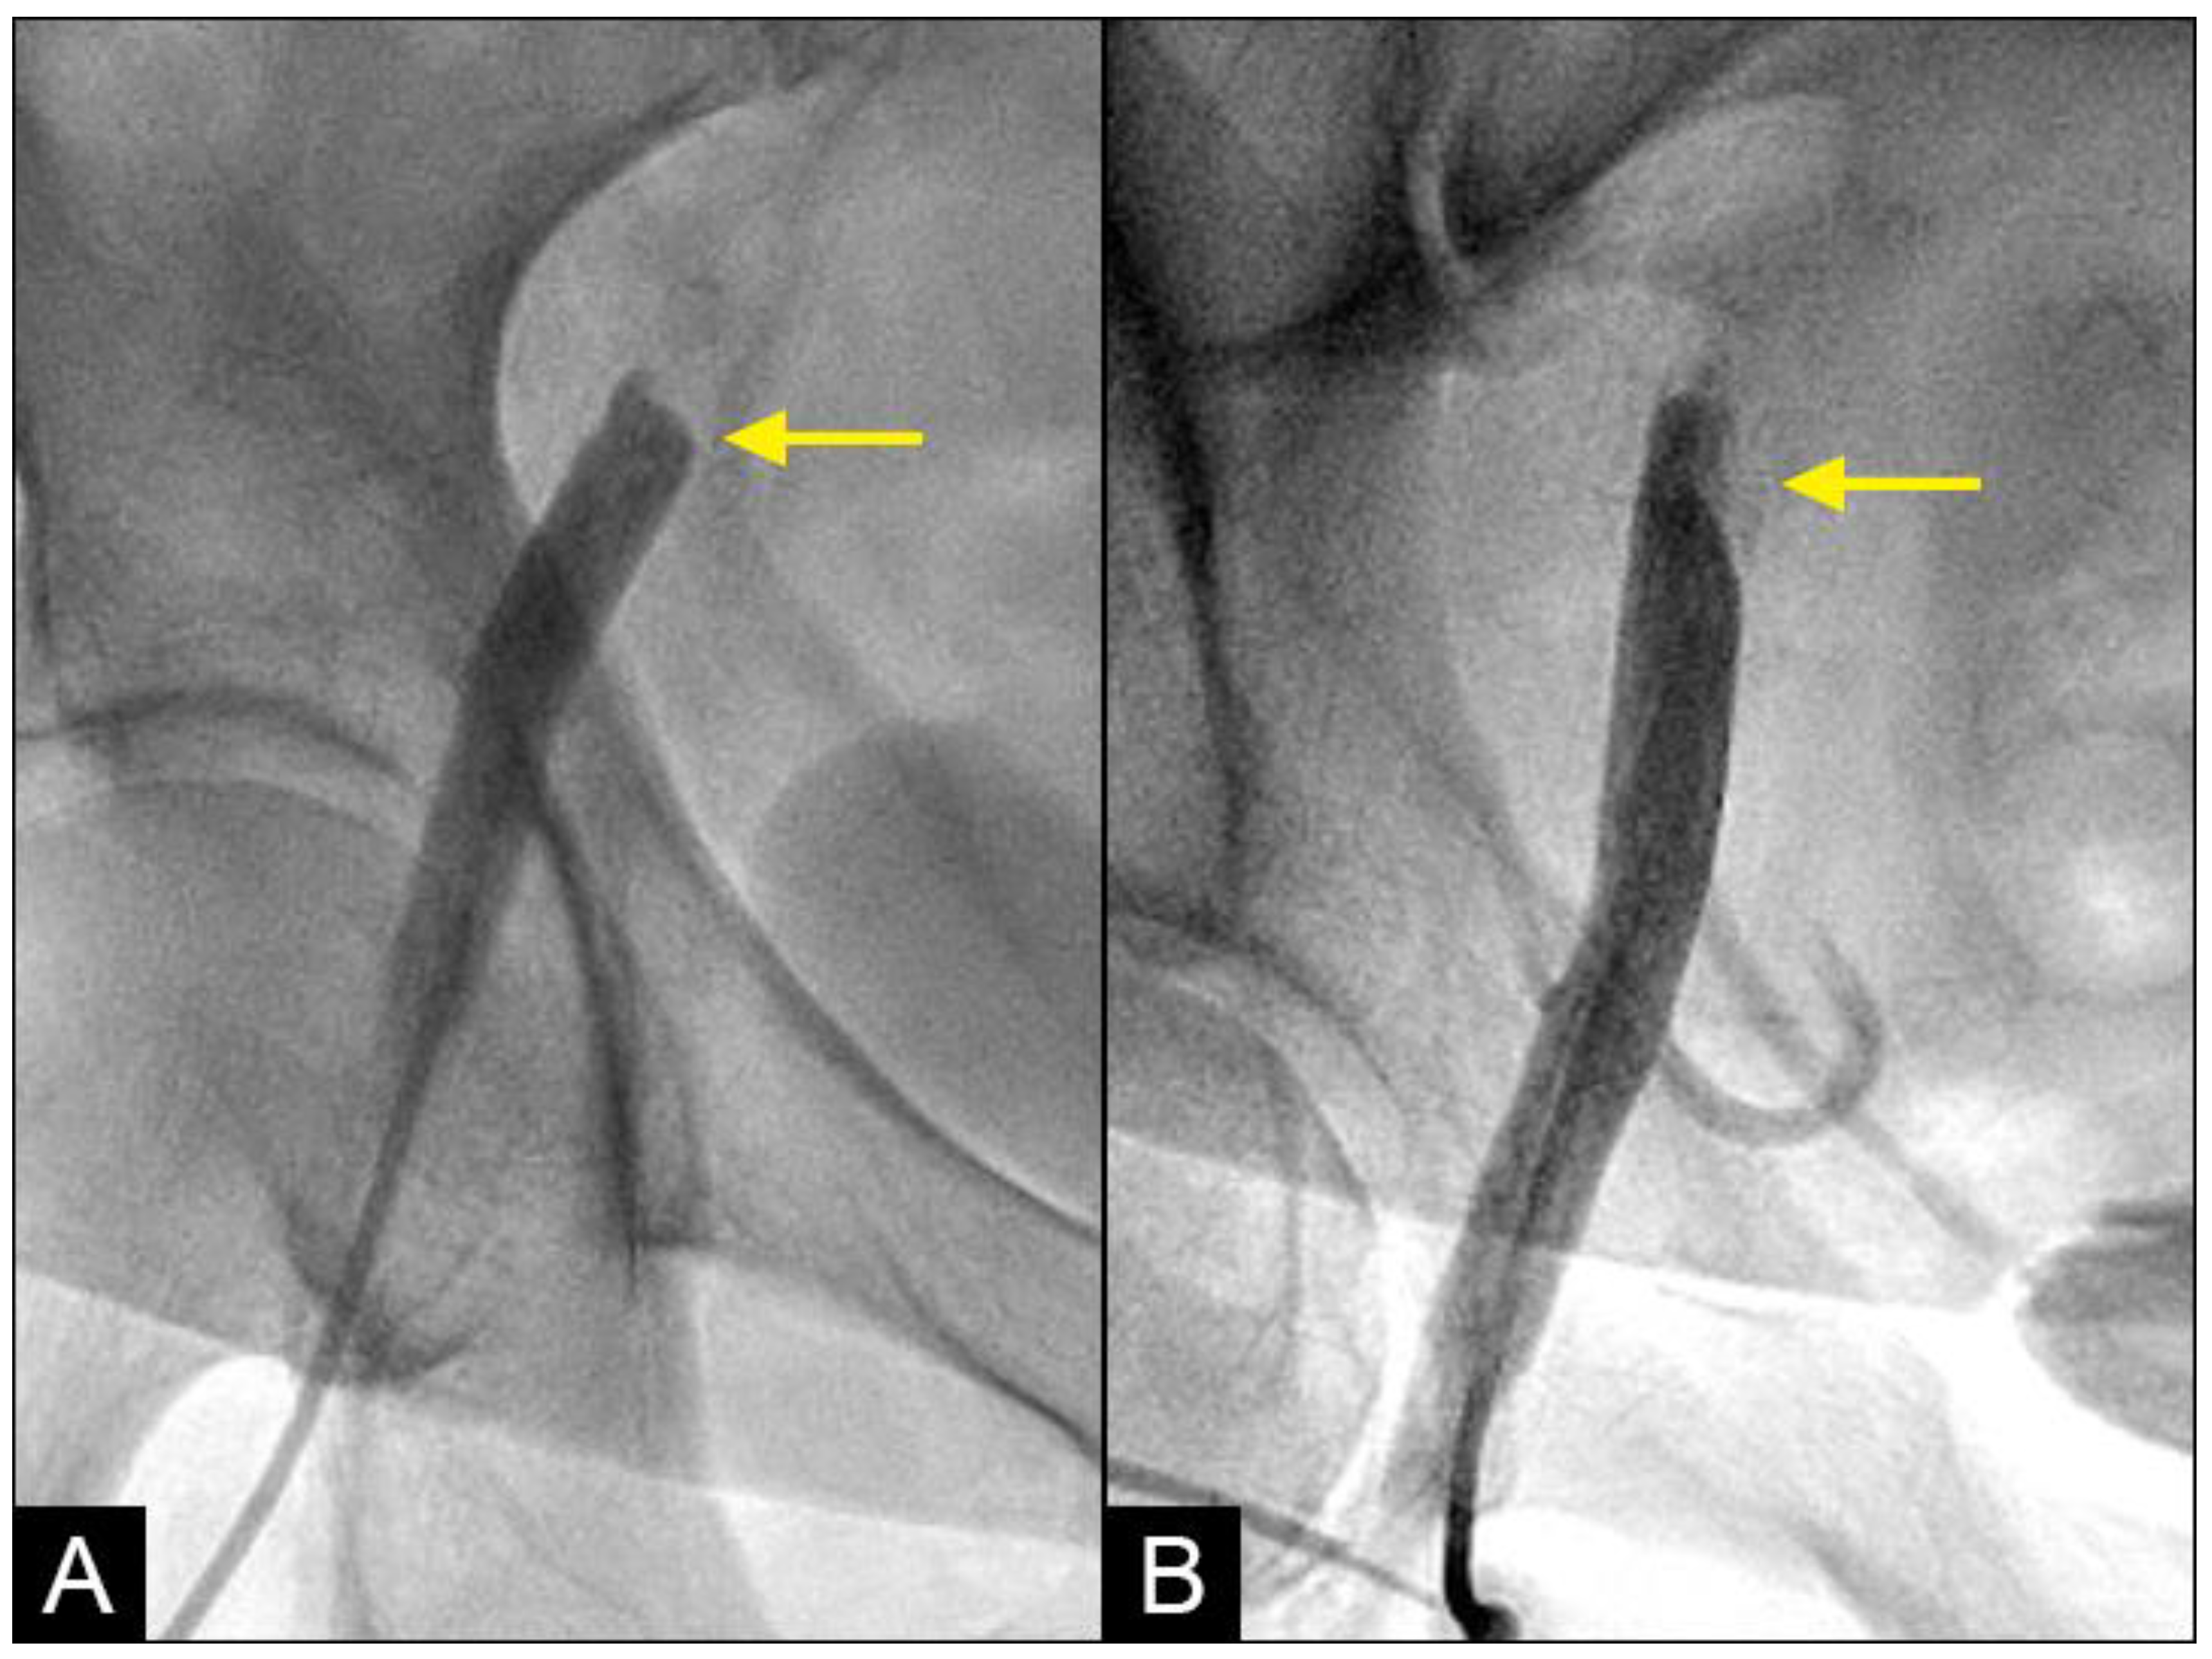

At the interface site, there were multiple levels of clashes depending on the level of blood pressure (BP). In cases of both severe systolic and diastolic hypertension (with systolic blood pressure (BP) > 160 mmHg and diastolic BP > 90 mmHg), the interface displayed a flat demarcation line, indicating a strong interaction between uncontrolled diastolic BP (DBP) and systolic BP (SBP) (Figure 7A). In cases of controlled SBP and elevated DBP, the interface appeared with a round proximal head (Figure 7B). In cases where diastolic BP was well controlled (<80 mmHg), there was no retrograde flow.

Figure 7.

(A,B) Interface of the collision between the antegrade blood flow and the retrograde contrast flow. The antegrade flow represents the systolic contraction, while the diastolic contrast flow represents the exaggerated peripheral vascular resistance or diastolic blood pressure (DBP). In patient (A), the systolic BP at the time of the iliac angiogram was 185/100 mmHg, while in patient (B), it was 120/90 mmHg.